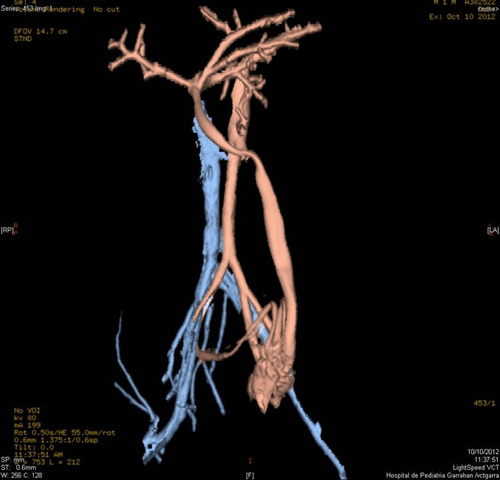

A 20-day-old male neonate with an umbilical hernia was referred to our hospital because of persistent wet umbilicus. Umbilical examination showed a 2 cm diameter umbilical hernia and a long epithelialized pulsatile cord with granulomatous tissue at its end (Fig. 1). Palpable thrill was note at the midportion of the umbilical cord. Doppler ultrasonography revealed a mass at the end of the umbilical cord harboring dilated blood vessels with turbulent blood flow (Fig. 2). This vascular mass continued to the umbilical vein, which was dilated and flowed into the liver. Abdominal contrast-enhanced computed tomography revealed umbilical AVM; the umbilical arteries were patent from both internal iliac arteries, flowed into the mass directly at the end of the umbilical cord, and the dilated umbilical vein flowed out from the mass, continuing from the umbilicus to the umbilical part of the portal vein in the liver (Fig. 3, 4).

Figure 4: Umbilical AVM with inflow from the umbilical arteries and outflow via the umbilical vein. |